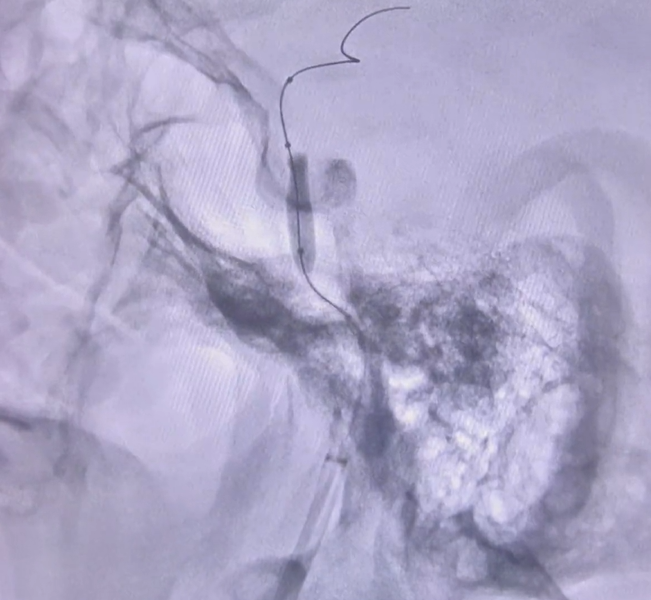

DSA示右侧颈内动脉次全闭塞

术中采用"先清淤、后修路、再架桥"的阶梯式策略:

(1) 精准通路建立,分阶段“清淤”, 球囊辅助通过+机械抽吸,成功捕获颈动脉两条暗红色血栓(4cm及1cm)。

(2) 阶梯式血管成形:"球囊序贯扩张"修复通路。复查造影示:前向血流明显改善,但仍有狭窄。

球囊序贯扩张

(3) 精准支架植入:为血管架起"长期保护桥",复查造影示:支架贴壁良好,管腔通畅,无残余狭窄。